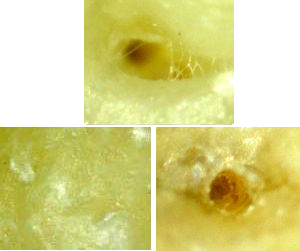

Nach der Extraktion wurde der 16 zur Reinigung eine Stunde lang in NaOCl (1%) gelegt. Da erschienen bei der palatinalen und bukkomesialen Wurzelspitze zwei offene Wurzelkanäle! Diese haben wahrscheinlich schon seit Jahren eine ganz kleine Menge Bakterien beherbergt.

▶ Der Wurzelkanal der bukkodistalen Wurzel (bd) ist biologisch perfekt verschlossen.

▶ Die Wurzelkanal der bukkomesialen Wurzel (bm) ist etwa 0.2 mm weit offen und wäre ohne die

Wurzelbehandlung noch kleiner geworden.

▶ Die palatinale Wurzel (pal) wurde instrumentell erweitert (kreisrunde Form) und dann mit

AH26 gefüllt. Das AH26 ist dann aber verschwunden. Es hat eine dunkle Verfärbung hinterlassen

und einen Platz für Bakterien freigegeben, welche die Sinusschleimhaut entzünden konnten.

Keine Wurzelfüllung kann den Apex so perfekt verschliessen wie der Nerv selber bei dieser bukkodistalen Wurzel (bd). Mit den Jahren werden Tausende von Bakterien im Blut an den apikalen Leerräumen der wurzelbehandelten Zähne (bm und pal) vorbeigeschwemmt.